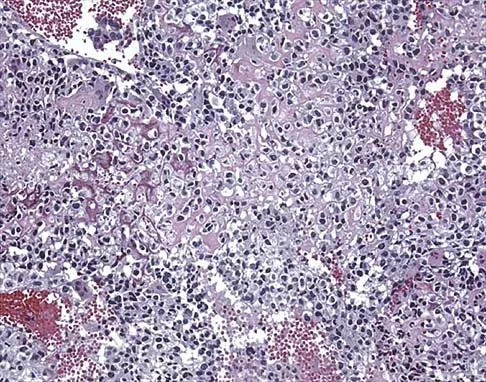

A 34-year-old woman reports constant midlateral arm pain after sustaining minimal trauma to the shoulder. Radiographs and a biopsy specimen are shown in Figures 29a and 29b. What is the most likely diagnosis?

Explanation

Eighty percent of giant cell tumors occur in patients older than age 20 years, with the peak incidence in the third decade of life. Most of these tumors are eccentrically located and epiphyseal in location. They are lytic in nature as in this patient. Although named for the hallmarked multinucleated giant cells seen in the lesion, the basic cell type is the spindle-shaped stromal cell. Chondroblastoma is highly cellular and contains large multinucleated giant cells with intercellular chondroid material, some of which is calcified. Chondromyxoid fibroma has chondroid tissue separated by strands of more cellular tissue with occasional multinucleated giant cells. Desmoplastic fibroma is characterized by poorly cellular fibrous tissue, and lymphoma is highly cellular with characteristic round cells. Campanacci M, Baldini N, Boriani S, et al: Giant cell tumor of bone. J Bone Joint Surg Am 1987;69:106-114.